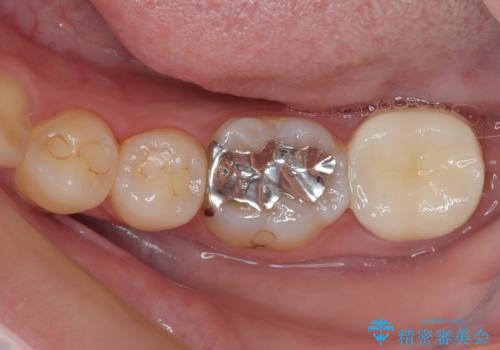

- 過去の歯医者通いの恐怖から虫歯を放置してきたものの、一大決心して来院された患者様です。

神経組織の失活している歯や歯根だけが残っている歯などがあり、全体的に歯石も多く付着している状態でした。

まずは歯石除去とブラッシング方法などの衛生指導を徹底的に行って口腔内環境を改善し、汚れの溜まりやすくなっている親知らずは全て抜去することとしました。

その後、歯根だけとなっている歯はインプラントに、神経組織の失活している歯は根管治療を行い、いずれもオールセラミッククラウンにて補綴治療を行うこととしました。